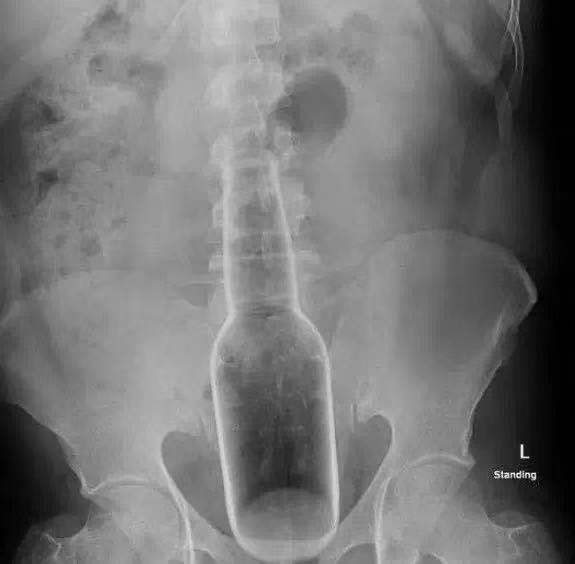

นายแพทย์หลิน หมอที่ดูแลเคสนี้ ได้ตรวจสอบดูรูทวารของเหวิน พบเห็นวัตถุบางอย่างอยู่ลึกจากรูทวารเข้าไปราว 2 นิ้ว จากนั้นจึงได้ทำการเอกซเรย์ดู ก็พบขวดแก้ว ความยาว 18 เซนติเมตร อยู่ในอุ้งเชิงกรานของเหวิน ซึ่งก้นขวดอยู่ห่างจากรูทวารของเหวินประมาณ 2 นิ้ว

หมอหลินได้ทำการผ่าตัดถ่างก้นเหวิน นำขวดแก้วดังกล่าวออกมาทันที ซึ่งทุกอย่างผ่านพ้นไปได้ด้วยดี ขวดแก้วผลุบออกมาโดยง่ายและใช้เวลาไม่นาน รายงานระบุว่า ขวดแก้วดังกล่าวเป็นขวดบรรจุยากันยุงแบบจีน รวมทั้งใช้เป็นยาแก้คัน ทั้งนี้ เคราะห์ดีที่มันเป็นขวดเปล่าแล้ว ไม่มีน้ำยาอยู่ข้างใน